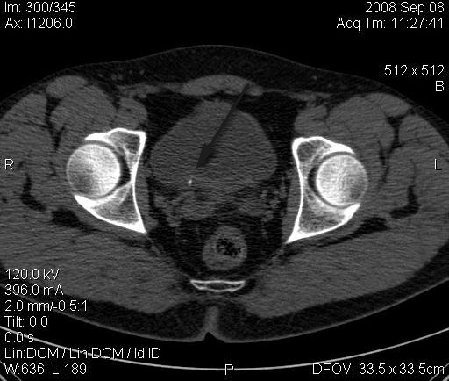

Re: КТ Почек. Почечная колика

Почечная колика; на последнем аксиальном скане чётко виден мелкий (2 мм) камень в устье правого мочеточника.

Для невладеющего КТ,очень четка видна аномалия на 3-4х снимках.А вот на 4-м скане в проксим.сегменте цистоида тоже есть гиперденсное точечное образование-не камень случайно?